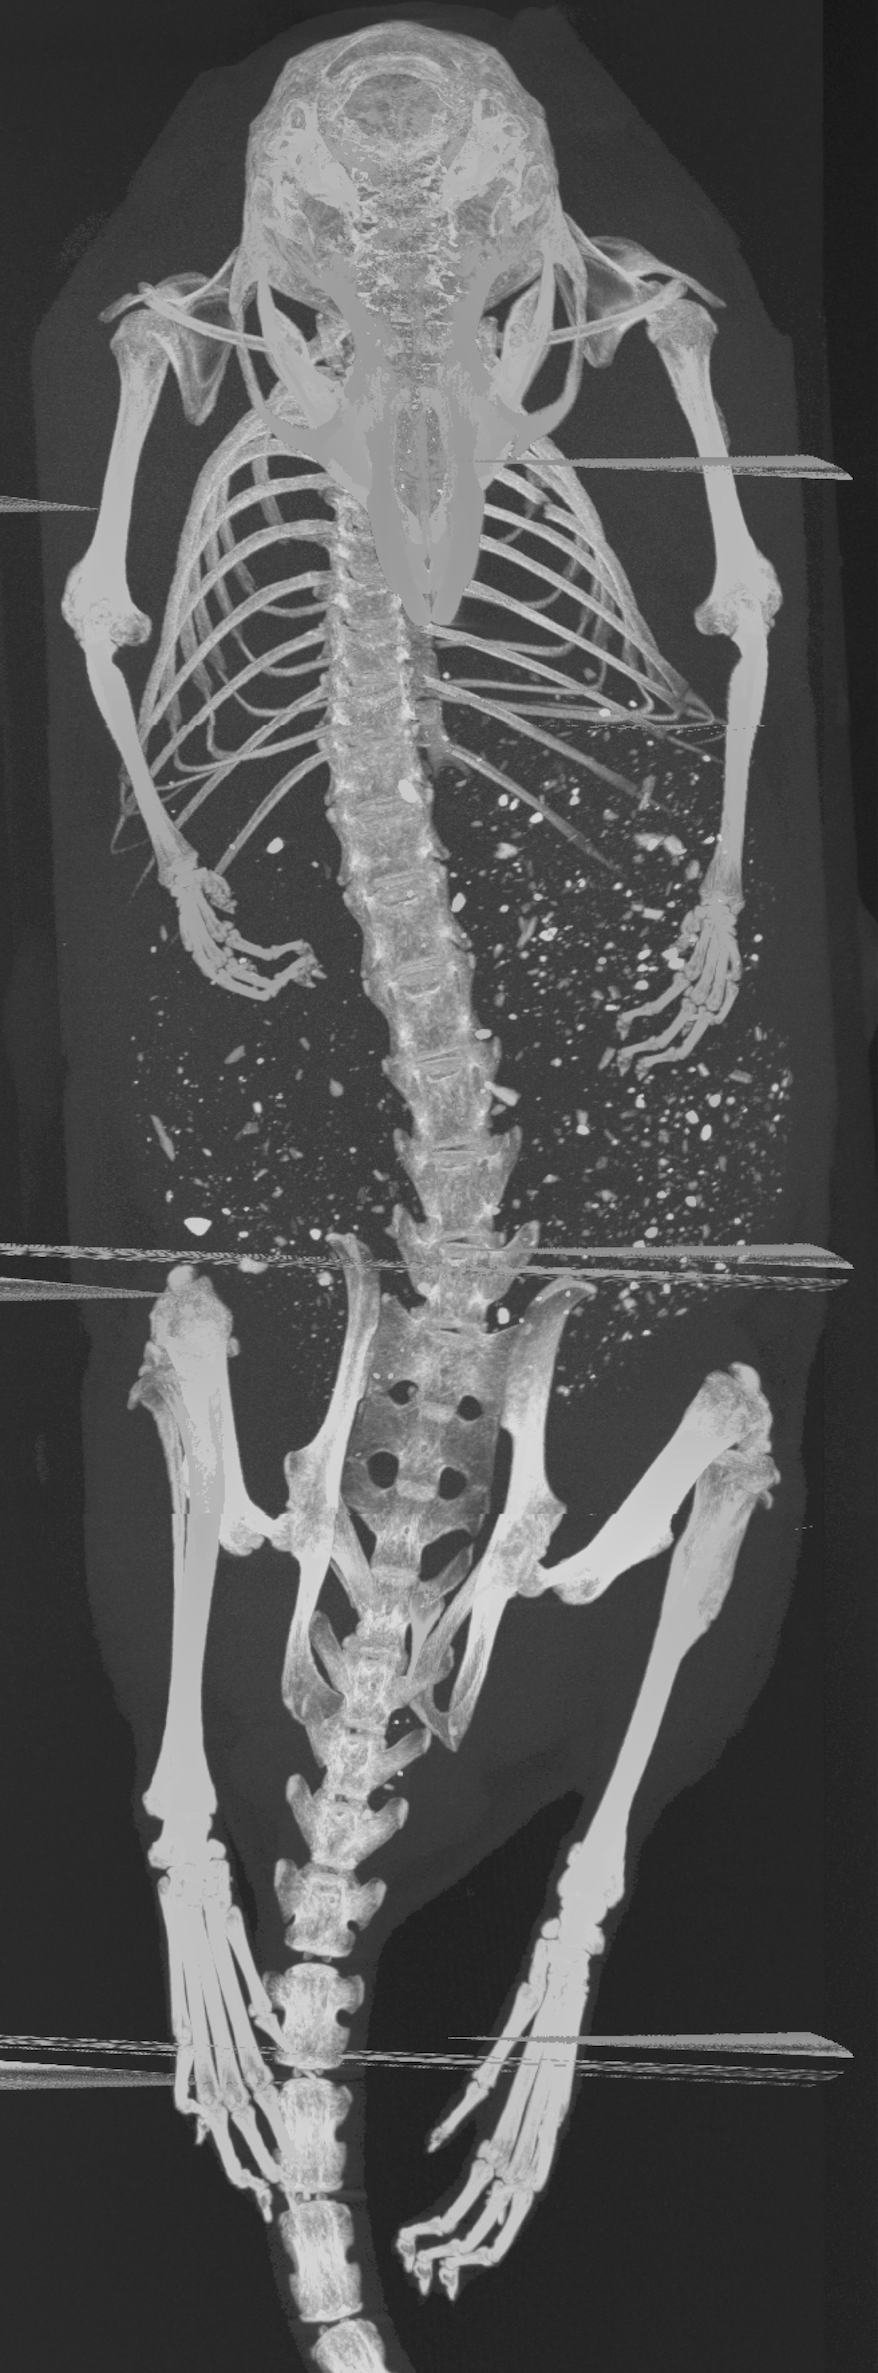

We received two of the mice, hereinafter labeled as A and B, from the UCSF study. Mice A and B were injected with 202020 kBq of 225Ac-Macropa-PEG8(7)-YS5 and 225Ac-DOTA-YS5, respectively. Following injection, mice A and B were euthanized at 222 and 444 days, respectively. The mice were each housed in a 505050 mL falcon tube and stored in a freezer at 7superscript7-7^{\circ}C when not in use.

The two mice were each imaged in the coded aperture and Compton modes to determine the feasibility of using these modalities to assess the daughter redistribution of 225Ac in small animals. The coded aperture and Compton images are overlaid with CT scans. CT imaging was performed separately from the gamma-ray measurements using a MILabs U-CT system; thus, the co-registration is not precise. The following describes the experiments and results in more detail.

In the case of mouse B, the coded aperture and Compton experimental setups were identical to those shown in Fig. 6. The coded aperture measurement of mouse B took place at 444 days post-injection, and data were acquired for 120120120 minutes at each 45superscript4545^{\circ} viewing angle. The total imaging time amounted to 161616 hours, and 3.9×1033.9superscript1033.9\times 10^{3} events were acquired on average at the 218218218-keV emission line of 221Fr at each rotation. The Compton measurement of mouse B took place at 666 days post-injection, and data were acquired for 707070 minutes at each 45superscript4545^{\circ} viewing angle. The total imaging time amounted to 9.39.39.3 hours, and 1.6×1031.6superscript1031.6\times 10^{3} events were acquired on average at the 440440440-keV emission line of 213Bi at each rotation.

Using ML-EM with TV, the two mice were reconstructed in 3-D from the coded aperture and Compton data at the 218218218-keV emission line of 221Fr and 440440440-keV emission line of 213Bi, respectively. Both the coded aperture and Compton images were generated from all eight projections after 250250250 iterations. Figs. 7b-c and 8b-c show the maximum intensity projections (MIP) of the gamma-ray images of mice A and B, respectively. These images are fused with a CT MIP. Furthermore, Figs. 7e-f and 8e-f show coronal slices of the gamma-ray images of mice A and B, respectively. These images are fused with a coronal CT image. The quantification factor, determined from the phantom measurements in Section III-A, was applied to each image so that the intensity scale is in units of percent injected activity per cubic centimeter (%IA/cc). Additionally, the intensity scales are decay corrected to the day of injection.

Figure 8: (a) CT MIP of mouse B fused with the (b) coded aperture (CA) and (c) Compton (CI) MIPs. (d) CT coronal slice of mouse B fused with coronal slices of the (e) CA and (f) CI images. The CA image was generated from a total of 3.1×1043.1superscript1043.1\times 10^{4} events at 218218218 keV, and the CI image was generated from a total of 1.2×1041.2superscript1041.2\times 10^{4} events at 440440440 keV. The intensity scales are decay corrected to the day of injection.